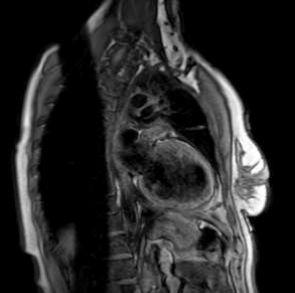

On a routine TTE follow-up, a highly mobile small mass attached to the anterolateral left ventricular wall was detected (Image.1 -2). Thrombus was the initial suspicion and the  patient was placed on oral anticoagulants and referred for further evaluation with cardiac magnetic resonance.

Image 2. Mass attached to anterolateral left ventricular wall